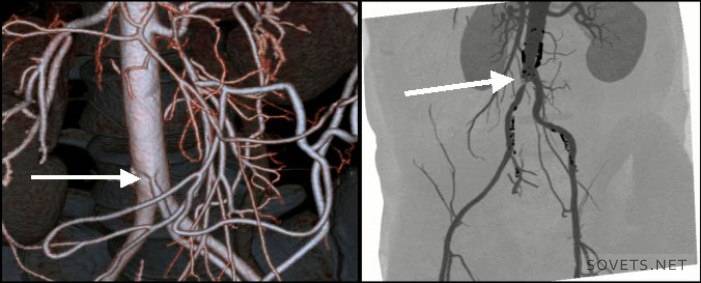

- Obtendo imagens espaciais 3D mais precisas. Modelos tridimensionais mostram com mais precisão a natureza e a localização da patologia. O uso de técnicas de escaneamento em espiral permitiu o uso da angiografia, ou seja, estudo das artérias, para identificar aneurismas vasculares, estreitamento, seu comprimento.

- Doenças dos vasos e gânglios linfáticos